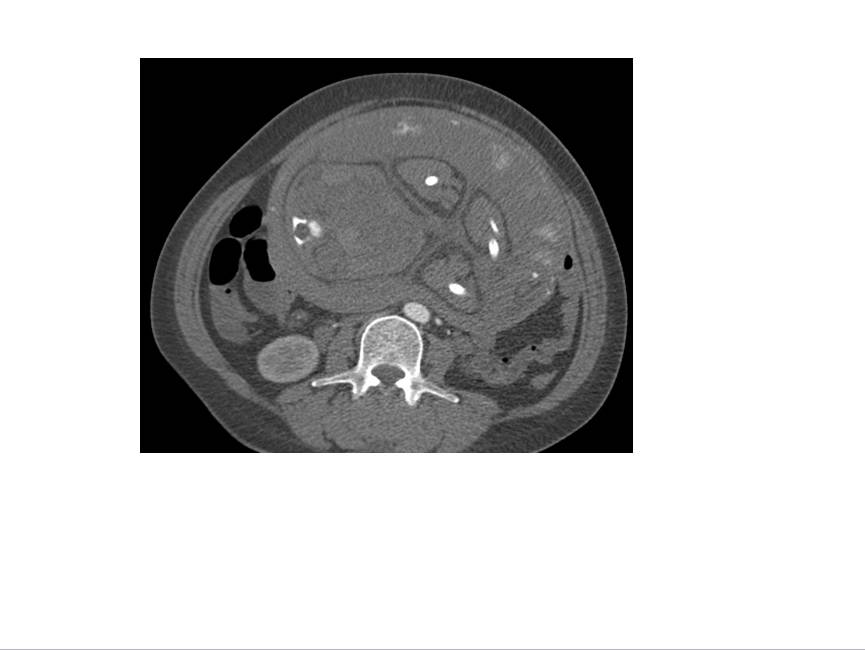

CT表现:自主动脉根部起至腹主动脉肾动脉水平可见撕裂之动脉内膜瓣影,子宫腔内可见胎儿影。

诊断结果:妊娠合并主动脉夹层(I型)。

1、撕裂的内膜瓣:多表现为弯曲的线样低密度影,部分患者可见多个破口,内膜漂浮在管腔中。

2、破口的显示:表现为真腔和假腔之间沟通的管道,薄层的横断图像,,多平面重组技术有助于破口的显示,有时因血栓的形成或撕裂情况复杂显示困难。

3、真、假腔的显示:真假腔可同时显影,或假腔强化和排空比真腔延迟;假腔内常有血栓形成可呈略高密度影,当多个破口存在时,真假腔较难区分。一般情况下假腔较大,真腔较小。